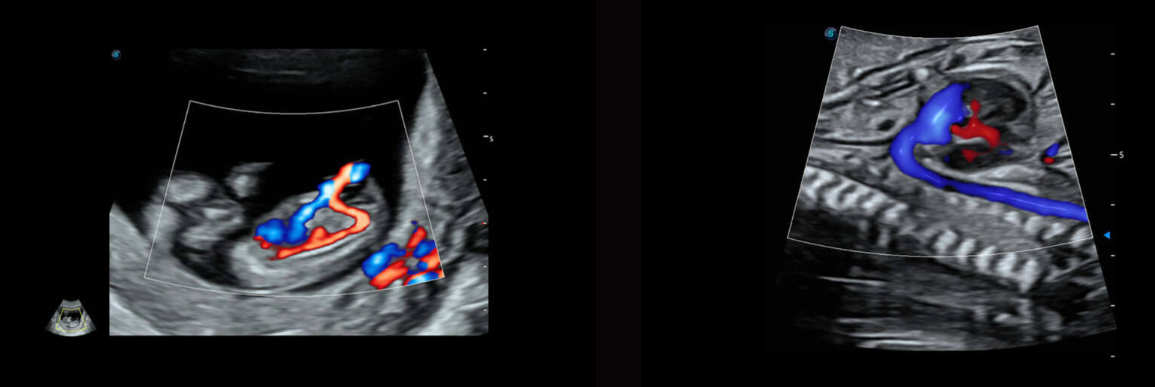

AVC-Follicle

Tính toán thể tích tự động cho nang trứng

Tự động xác định và đo nhiều nang trứng từ hình ảnh thể tích 3D

Các nang trứng được tự động sắp xếp theo kích thước với mã màu

Tăng tốc báo cáo đánh giá nang trứng với đồ họa màu được thiết kế

Siêu âm cản quang tử cung vòi trứng 4D (HyCoSy):

HyCoSy 4D thời gian thực hỗ trợ các kỳ thi phụ khoa để đánh giá tình trạng thông vòi trứng theo cách trực quan và tự tin, đồng thời tăng cường khả năng hiển thị 3D hình thái tử cung và vòi trứng. Ngoài ra, quá trình tưới máu thời gian thực có thể nhìn thấy rõ ràng để biết thêm thông tin về chẩn đoán chính xác tình trạng thông vòi trứng.